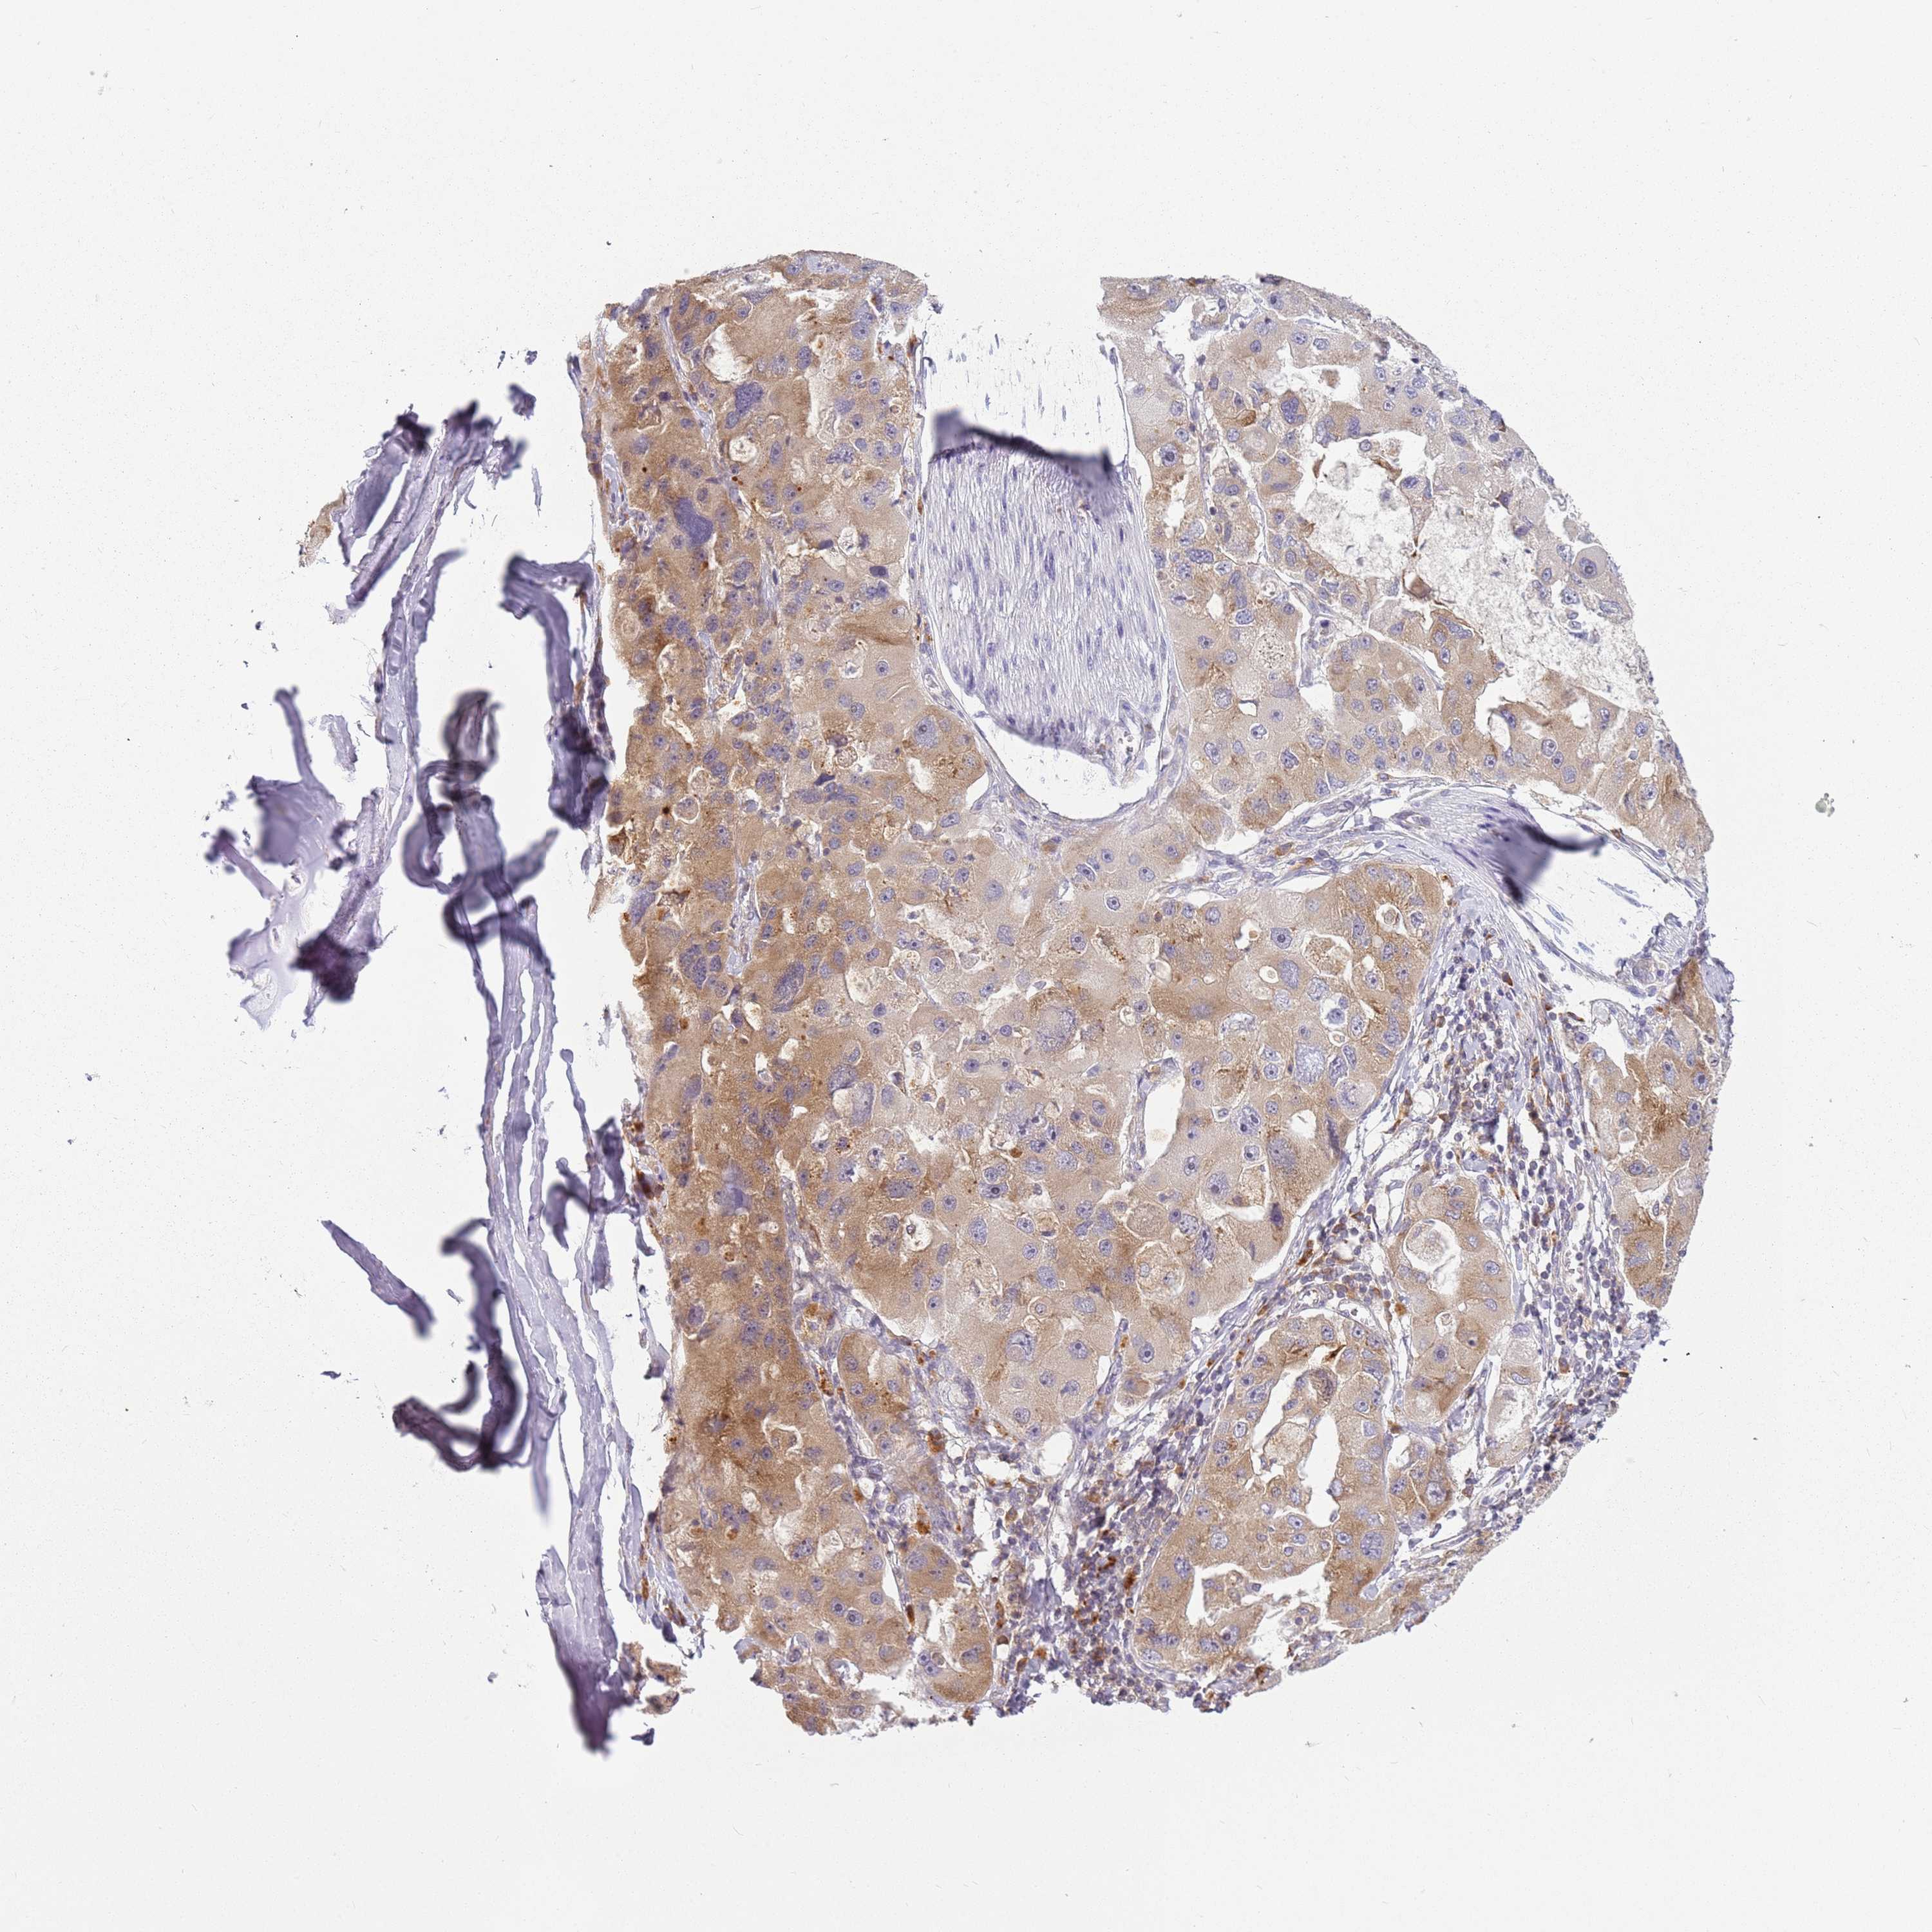

LUNG ADENOCARCINOMA (TCGA) - Interactive survival scatter ploti

The Survival Scatter plot shows the clinical status (i.e. dead or alive) for all individuals in the patient cohort, based on the same data that underlies the corresponding Kaplan-Meier plots. Patients that are alive at last time for follow-up are shown in blue and patients who have died during the study are shown in red.

The x-axis shows the expression levels (FPKM) of the investigated gene in the tumor tissue at the time of diagnosis. The y-axis shows the follow-up time after diagnosis (years). Both axes are complimented with kernel density curves demonstrating the data density over the axes. The top density plot shows the expression levels (FPKM) distribution among dead (red) and alive patients (blue). The right density plot shows the data density of the survived years of dead patients with high and low expression levels respectively, stratified using the cutoff indicated by the vertical dashed line through the Survival Scatter plot. This cutoff is automatically defined based on the FPKM cutoff that minimizes the p-score. The cutoff can be changed by dragging the vertical line or by entering a cutoff value in the square labeled "Current cut-off".

Under the Survival Scatter plot the p-score landscape (black curve; left axis) is shown together with dead median separation (red curve; right axis). Dead median separation is the difference in median mRNA expression between patients who have died with high and low expression, respectively. It is calculated as follows: median FPKM expression of dead patients with high expression - median FPKM expression of dead patients with low expression. This is intended to aid the user in visually exploring custom cutoffs and the associated p-scores and dead median separation.

Individual patient data is displayed and can be filtered by clicking on one or more of the category buttons on the top of the page. Categories describing expression level and patient information include: high, low, alive, dead, female, male and tumor stages. The scale of the x-axis can be toggled between linear and log-scale by clicking on the "x log" button. Mouse-over function shows TCGA ID, patient information and mRNA expression (FPKM) for each patient.

& Survival analysisi

Kaplan-Meier plots summarize results from analysis of correlation between mRNA expression level and patient survival. Patients were divided based on level of expression into one of the two groups "low" (under cut off) or "high" (over cut off). X-axis shows time for survival (years) and y-axis shows the probability of survival, where 1.0 corresponds to 100 percent.

RPS28 is not prognostic in Lung Adenocarcinoma (TCGA)

Stage:

Survival analysis

Current cut offi

Current cut-off shows the cut-off (FPKM) currently selected. It may be changed manually. When the current cut-off is changed, the vertical dashed line indicating cut-off, the interactive survival scatter plot and the Kaplan-Meier curve will be automatically adjusted to show results accordingly.

:

Best expression cut offi

Based on the FPKM value of each gene, patients were classified into two groups and association between prognosis (survival) and gene expression (FPKM) was examined. The best expression cut-off refers the FPKM value that yields maximal difference with regard to survival between the two groups at the lowest log-rank P-value. Best expression cut-off was selected based on survival analysis .

When clicking on this number, the vertical dashed line indicating cut-off, the interactive survival plot, and the Kaplan-Meier curve will be adjusted to show results based on the best expression cut-off.

: 110.31

Median expressioni

Median expression refers to the median FPKM value calculated based on the gene expression (FPKM) data from all patients in this dataset. When clicking on this number, the vertical dashed line indicating cut-off, the interactive survival plot, and the Kaplan-Meier curve will be adjusted to show results based on the median expression.

: N/A

Median follow up timei

Median follow up time refers to the median time (years) after diagnosis with this type of cancer, based on clinical data from all patients in this dataset.

P scorei

Log-rank P value for Kaplan-Meier plot showing results from analysis of correlation between mRNA expression level and patient survival.

N/A

5-year survival highi

5-year survival for patients with higher expression than the expression cutoff.

For melanoma and glioma, 3-year survival is shown.

5-year survival lowi

5-year survival for patients with lower expression than the expression cutoff.

TCGA RNA samplesi

RNA-seq data is reported as average FPKM (number Fragments Per Kilobase of exon per Million reads), generated by the The Cancer Genome Atlas (TCGA) .

Normal distribution across the dataset is visualized with box plots, shown as median and 25th and 75th percentiles. Points are displayed as outliers if they are above or below 1.5 times the interquartile range. FPKM values of the individual samples are presented next to the box plot.

Average pTPM 156.7

Number of samples 497